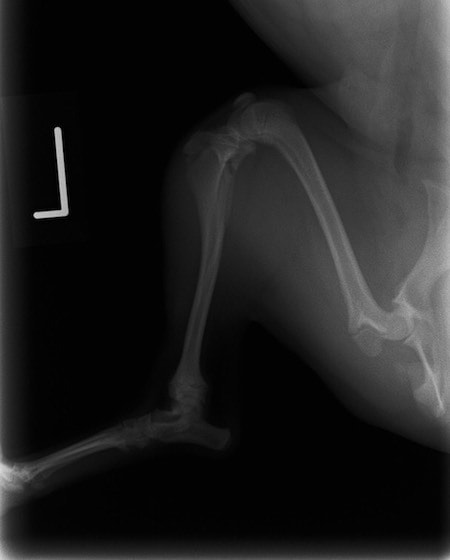

症例:交通事故による椎体脱臼

柴犬:9歳、避妊雌

交通事故直後、胸腰部に激しい疼痛、両後肢に完全麻痺を認め、シェフシェリントン徴候を呈していました。レントゲン検査において、第11-12胸椎間の脱臼が認められました。

脊髄の減圧、脊柱管の再構築・安定化を目的に、片側椎弓切除術およびMatrixMANDIBLE Plateによる椎体固定を実施しました。

隣接椎体を架橋するようにプレートを設置しました。

術後レントゲン写真